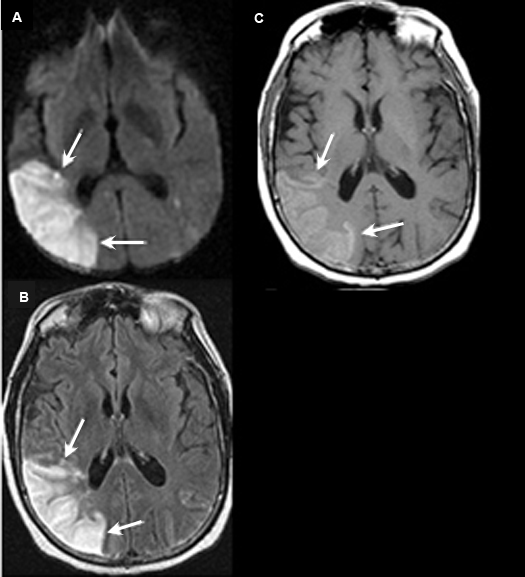

Figure 5 A-C: MR Images

|

Posterior cerebral artery territory Acute Stroke

Case 5:

Imaging findings: Figure 5 A-C

- Pre-contrast axial T1 wtd. MRI

- Axial flair image

- Post-contrast axial T1 wtd. MRI

Acute infarction is seen involving the left occipital lobe (yellow arrow) and adjacent left temporal lobe (white arrow). The left posterior cerebral artery territory infarction is better seen on flair sequence (Fig. B) than on T1 wtd. pulse sequence (Figs. A, C).